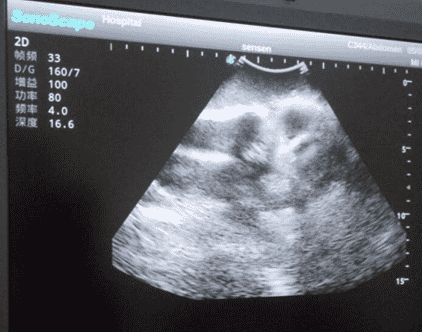

This model is an ideal choice for ultrasound-guided knee arthrocentesis training with true-to-life skin feel and touch, accurate anatomical structures as well as real clinical ultrasound images. Realistic resistance to needle tips and correct landmarks provide excellent hands-on experience.

2)   Real clinical ultrasound images with clear anatomical structures like femur, joint cavity, etc.